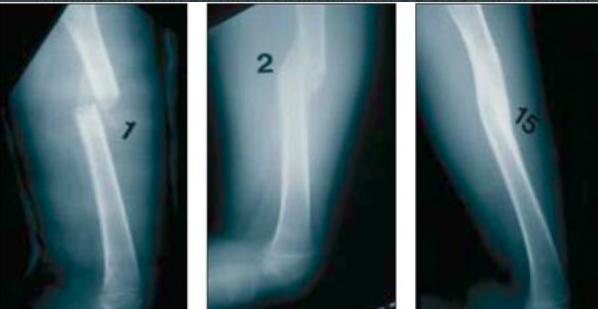

كسور الأطفال